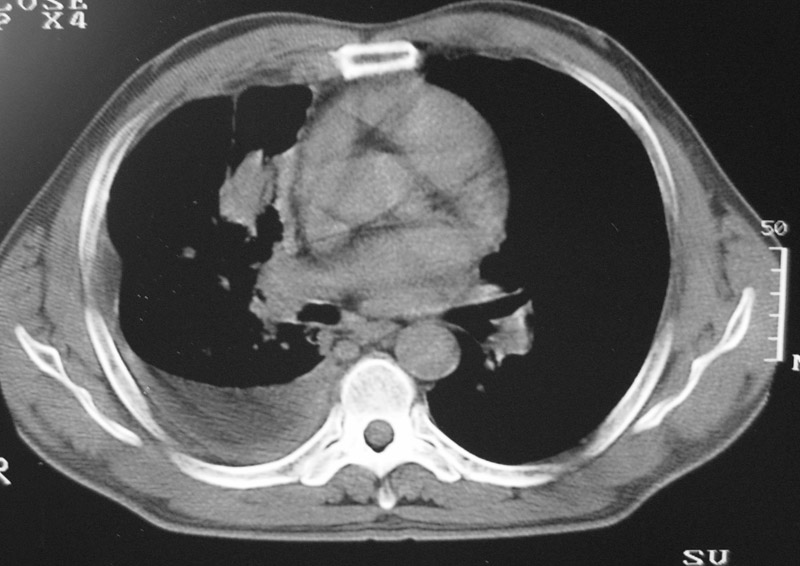

以下是引用守望可可西里在2006-9-11 15:29:00的发言:[br][br] ct平扫表现:右侧胸膜腔缩小,积液,胸膜增厚且不均匀、不规则,以纵隔胸膜增厚为主,边缘呈锯齿状,并见附壁内突之结节状肿块影。右肺含气量减少,纹理聚集,右肺门中下部见数个肿大的淋巴结。纵隔无移位,内未见明显肿大淋巴结,双侧主支气管以及各叶、段支气管比较通畅。。[br] 考虑:右侧胸膜恶性间皮瘤,伴肺门淋巴结转移。